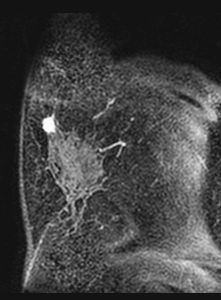

MRIによる乳腺腫瘍の評価

乳腺腫瘍の画像診断としてはマンモグラフィ、超音波、MRIが主として挙げられます。特にMRIにおいては、様々な撮像法が進歩し、形態や血管新生、血管透過性、間質の多寡などに加えて、細胞密度、腫瘍内代謝物質の検出などの形態とは異なる評価が可能になってきています。しかし、従来の研究は良悪性の鑑別、組織型推定や広がり診断に関するものが主でした。そこで、鑑別診断のみでなく、MRI所見と予後、予後因子との関連を検討し、画像所見により悪性度診断や予後予測が可能であるかの研究を行っています。術前に悪性度を判断することで、術前化学療法の併用の適応や術式決定に有用な情報を得られることが期待できます。